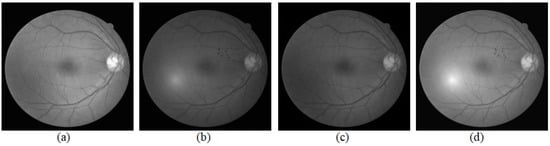

2. Preprocessing

2.1. Intensity Correction

2.2. Linear Interpolation